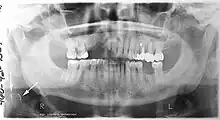

A dental panoramic radiograph, showing the maxilla and mandible, all the teeth including the "wisdom teeth," the frontal and maxillary sinuses, the nasal cavity and the temporomandibular joint and other near by head and neck anatomy.